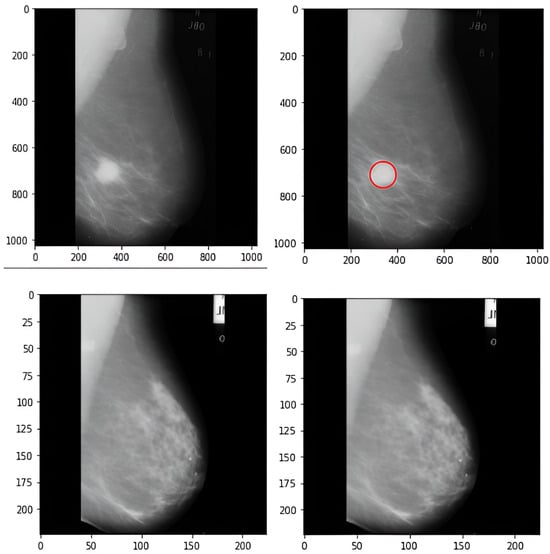

5.2. Localization